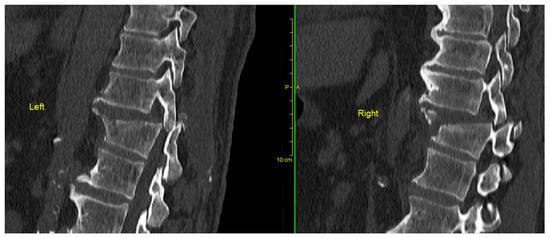

Figure 2.

Preoperative CT scan showing a bilateral locked facet fracture–dislocation of the Th11–Th12 levels. The tips of the superior facet joints were also fractured indicating the high violence of the injury causing bilateral locked facet dislocation.